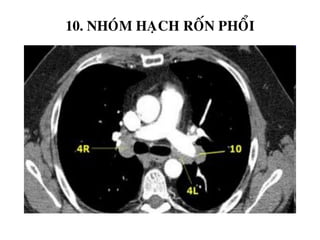

10. NHOÙM HAÏCH ROÁN PHOÅI